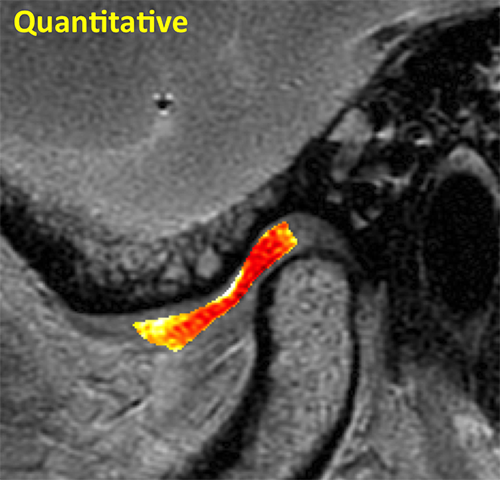

Tendon Quantitative

Quantitative MRI reveals marked changes in T2 values with bright signal centrally representing collagen fiber disorganization.